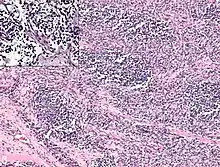

Photomicrograph showing nodules of tumor cells separated by hyalinised fibrous septae (50×, HE stain). Inset: Discohesive large tumor cells with hyperchromatic nucleus and scant cytoplasm (200×, HE stain). The diagnosis was postauricular congenital alveolar rhabdomyosarcoma.